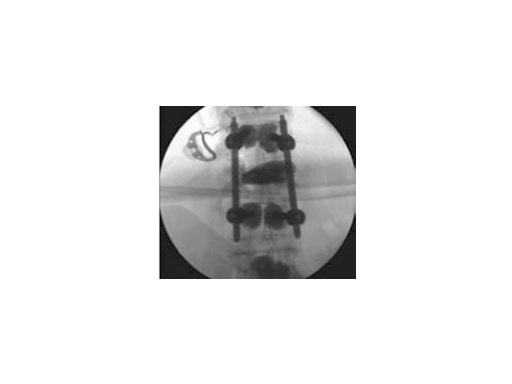

Synflate can be used stand-alone or in combination with posterior instrumentation (see the clinical cases within this article).

Both guide wire and trocar can be inserted through either a transpedicular (Fig 2a) or extrapedicular (Fig 2b) approach. The trocar allows access in a single step while the wire guide is first used to create a path for the access instruments.